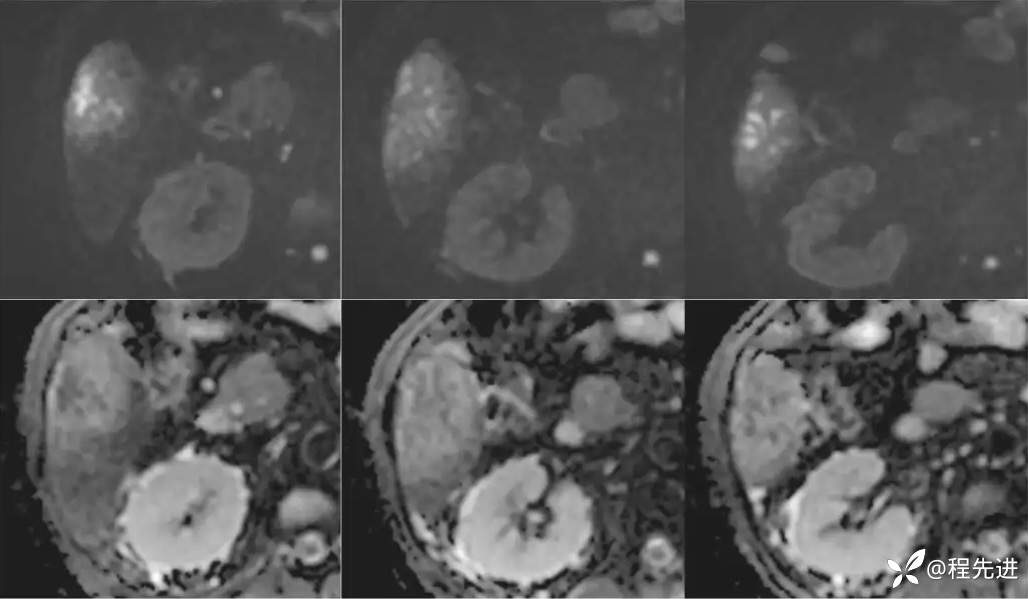

DWI、ADC

T1蒙片:

动脉期: